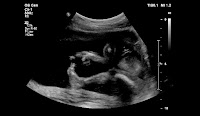

My labor lasted a total of 6.5 hours from the time my water broke to the birth of a healthy, beautiful daughter, Tevia Hazel Ogrins at 10:39am. She weighed 8 lbs 7.6 oz, and measured 21.75 inches in length.![]() |

| 1-day-old Tevia Hazel |